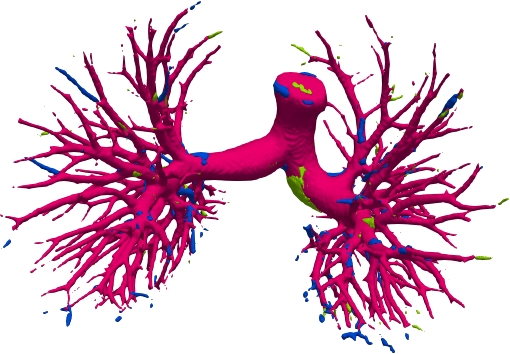

We qualitatively analyze our method on four challenging lung organ datasets. In Fig. 5, SFCN [19] suffers from severe false positives and some false negatives, especially for the big green areas of airway leakages. WNet [22] is mainly influenced by false negatives on the main trachea. For the Fibrosis dataset at the third row, it also encounters the false negative problem in the terminal bronchioles moderately. FANN [10] bears the slight discontinuity issue of false negative in the terminal bronchioles of BAS dataset, and the severe discontinuity and airway leakage problems on the more challenging Fibrosis benchmark. Instead, due to the above two novel modules, our method can solve the defects of false negative, discontinuity, and leakages faced by past advanced methods. Besides, the results on PARSE22 artery dataset in supplementary Fig. 6 also proves this.